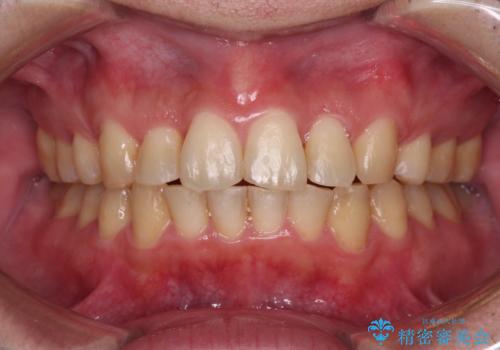

狭い上顎骨を拡大 著しい叢生を抜歯矯正で改善

- 上顎の著しい叢生と奥歯の咬みにくさを気にして来院された患者様です。

骨格的に上顎は狭く、下顎は右側にシフトしていたため、右側臼歯はクロスバイトとなっていました。

上顎骨を急速拡大装置により拡大し、ワイヤー装置による抜歯矯正治療を行うこととしました。